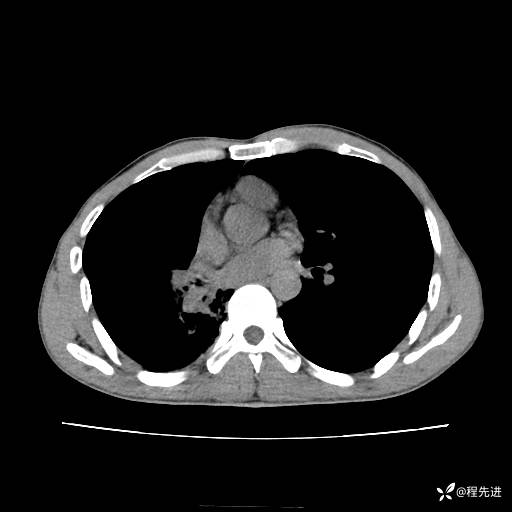

患者性别:男

患者年龄:49岁

主诉:咳嗽、胸痛1周

简要病史:1周前受凉感冒后开始出现咳嗽症状,阵发性连声咳,痰多,黄白痰,不易咳出,伴胸痛、气紧、胸闷,右侧为主,活动用力、呼吸时胸痛明显,曾在当地诊所贴敷膏药仍疼痛

体格检查:T:36.3 ℃ P:80 次/分 R:20 次/分 BP:120/88 mmHg,指脉氧饱和度97%,意识清晰,呼吸平稳,右侧第二、三肋骨压痛,可见膏药贴敷,皮肤无异常,双肺呼吸音粗,未闻及干湿性啰音。心率80次/分,节律整齐,无杂音。腹平软,全腹无压痛无反跳痛

临床诊断:社区获得性肺炎

CT平扫: